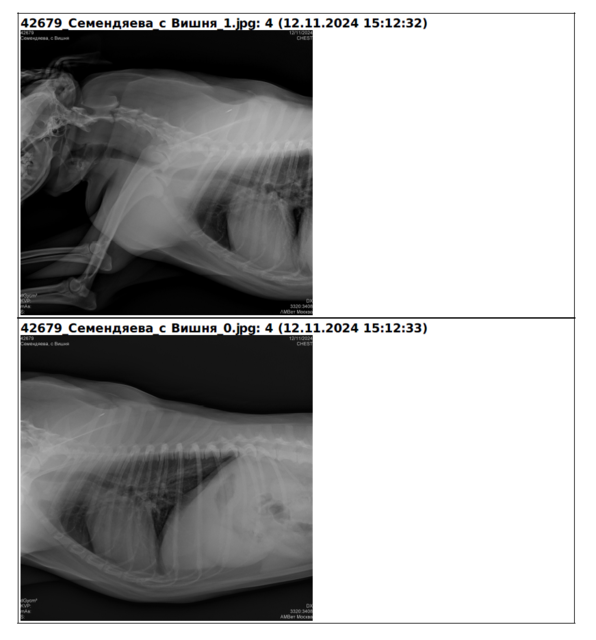

Мы решились и поехали к хорошему кардиологу Челышевой, в ветклинику Амвет. Все исследования по сердцу + ренгент легких, ничего не выявили. Признаки застарелого бронхита есть, но на данный момент никаких легочных заболеваний нет. Сердечной недостаточности нет.

А вот уже рентген пришлось мордочку перевязать.